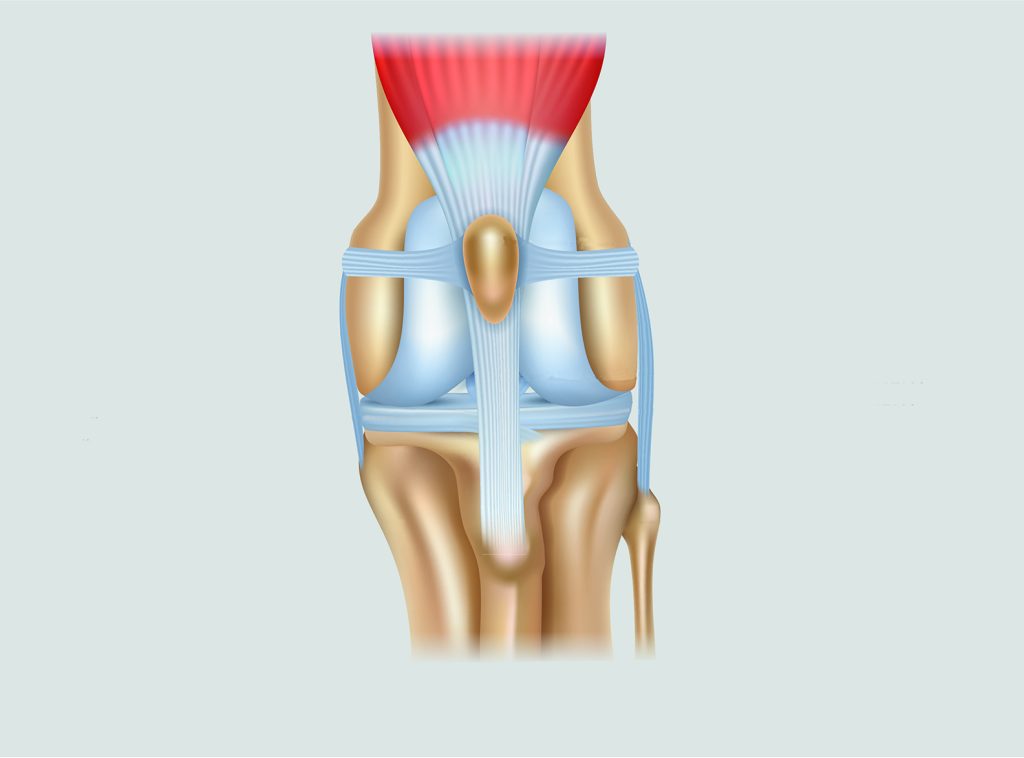

Patellaluxatie is een aandoening waarbij de knieschijf op de knie te los ligt, waardoor de knieschijf bij beweging buiten de groeve gaat. Normaal gesproken ligt de knieschrijf in de groeve van het dijbeen, de knieschijf zit via een pees vast aan een grote spier van het bovenbeen en aan de voorkant van het scheenbeen. Bij patellaluxatie schuift de knieschijf van de knie af en komt dan naast de knie te liggen.

Er zijn verschillende gradaties van patellaluxatie. Er zijn 4 graderingen van patellaluxatie:

- Kan manueel worden geluxeerd, maar de patella schiet zelf terug in de groeve.

- Patella luxeert intermitterend, en gaat niet vanzelf terug, kan wel teruggeduwd worden.

- Patella is permanent geluxeerd en kan manueel worden teruggeduwd.

- Patella is permanent geluxeerd en kan niet manueel worden teruggeduwd.